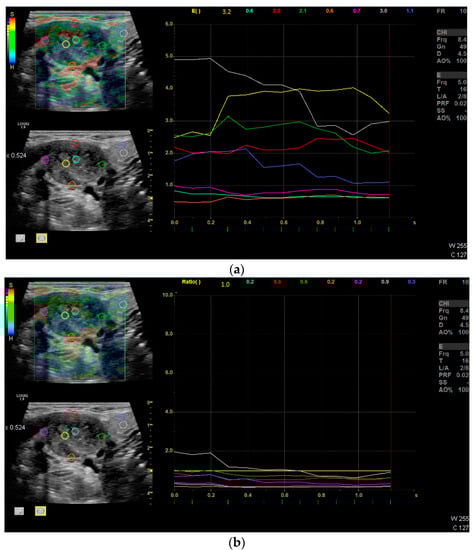

| Strain Elastography | Qualitative report of stiffness (soft or hard) | Q-analysis of strain elastography with Q-ratio; two ROI in the center, four at the margin of the LN and two in the surrounding soft tissue. The ROIs within the LN included areas with the lowest and the highest stiffness. The diameter of each ROI was 2–3 mm. |

| CEUS | Perfusion and enhancement dynamics (Wash-in/Wash-out) | Time–Intensity Curve analysis with Time-to-Peak and Area-under-the-Curve; two ROI in the center, four at the margin of the LN and two in the surrounding soft tissue (outside of vessels). For the correct placement of ROI, only positive values were accepted (adjustment for artefacts). The diameter of each ROI was 2–3 mm. Additionally parametric evaluation of the perfusion kinetics. |